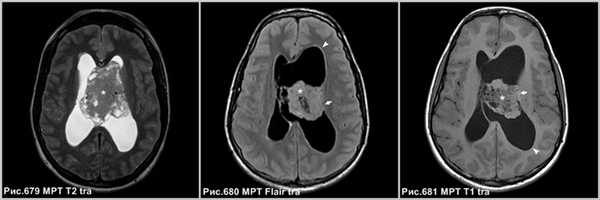

Центральная нейроцитома в виде неоднородной структуры объёмного образования, расположенного в боковом желудочке, связанное с прозрачной перегородкой (звёздочки на рис.679-681), сопровождающееся расширением бокового желудочка (головки стрелок на рис.680, 681). МРТ демонстрирует врастание опухоли в стенку бокового желудочка левого полушария большого мозга (стрелки на рис.680, 681).

На МРТ в режиме Т1 после контрастного усиления определяется неоднородное накопление контраста в солидных участках опухоли (головки стрелок на рис.682-684). В области внутриопухолевых кист усиление отсутствует.